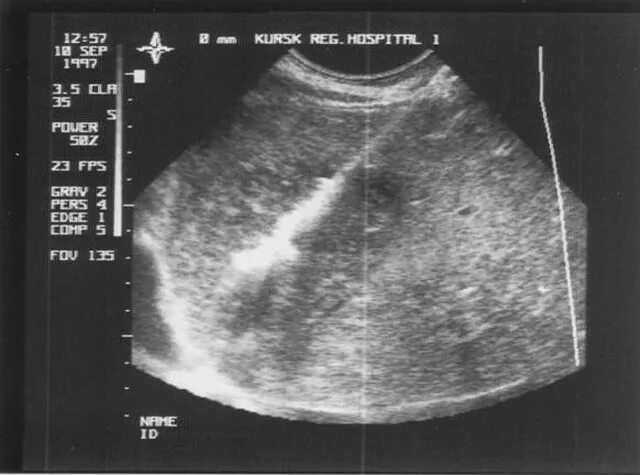

Анэхогенное включение неправильной формы